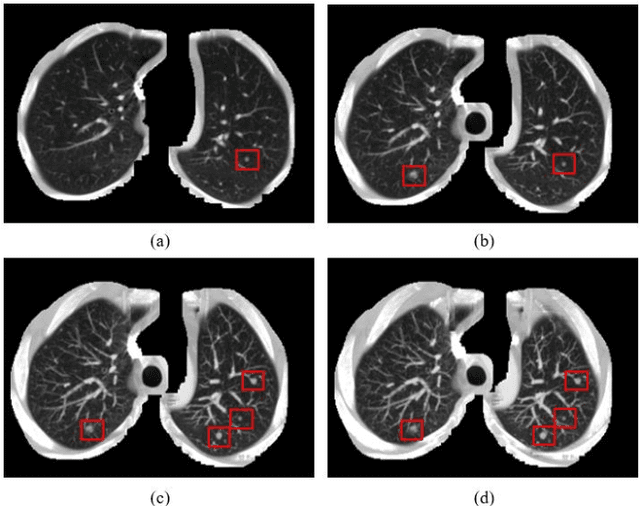

Abstract:Accurate pulmonary nodule detection in computed tomography scans is a crucial step in lung cancer screening. Computer-aided detection (CAD) systems are not routinely used by radiologists for pulmonary nodules detection in clinical practice despite their potential benefits. Maximum intensity projection (MIP) images improve the detection of pulmonary nodules in radiological evaluation with computed tomography (CT) scans. In this work, we aim to explore the feasibility of utilizing MIP images to improve the effectiveness of automatic detection of lung nodules by convolutional neural networks (CNNs). We propose a CNN based approach that takes MIP images of different slab thicknesses (5 mm, 10 mm, 15 mm) and 1mm plain multiplanar reconstruction (MPR) images as input. Such an approach augments the 2-D CT slice images with more representative spatial information that helps in the discriminating nodules from vessels through their morphologies. We use the public available LUNA16 set collected from seven academic centers to train and test our approach. Our proposed method achieves a sensitivity of 91.13% with 1 false positive per scan and a sensitivity of 94.13% with 4 false positives per scan for lung nodule detection in this dataset. Using the thick MIP images helps the detection of small pulmonary nodules (3mm-10mm) and acquires fewer false positives. Experimental results show that applying MIP images can increase the sensitivity and lower the number of false positive, which demonstrates the effectiveness and significance of the proposed maximum intensity projection based CNN framework for automatic pulmonary nodule detection in CT scans. Index Terms: Computer-aided detection (CAD), convolutional neural networks (CNNs), computed tomography scans, maximum intensity projection (MIP), pulmonary nodule detection